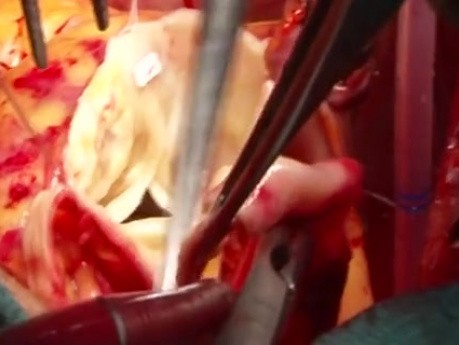

Dwoma głównymi powodami wymiany zastawki aortalnej są jej stenoza lub niedomykalność. Podczas zabiegu usuwa się zniszczoną zastawkę i zastępuje sztuczną - mechaniczną lub biologiczną. Zabieg zwykle wykonuje...

Wymiana zastawki aortalnej - technika operacyjna

Dwoma głównymi powoda i wymiany zastawki aortalnej są jej zwężenie lub niedomykalność. Podczas zabiegu uszkodzona zastawka jest zastępowana sztuczną - mechaniczną lub biologiczną. Zwykle zabieg wykonuje...